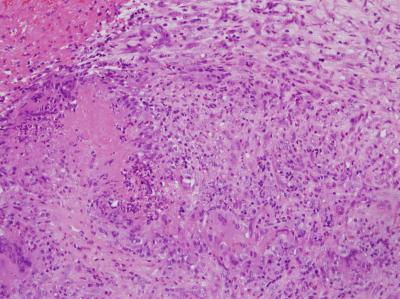

TB Prostate

FAZARINA M

Tan GH

Badrulhisham B

Shiran MS

Tan GC

genitourinary

prostate

tuberculosis

Case report